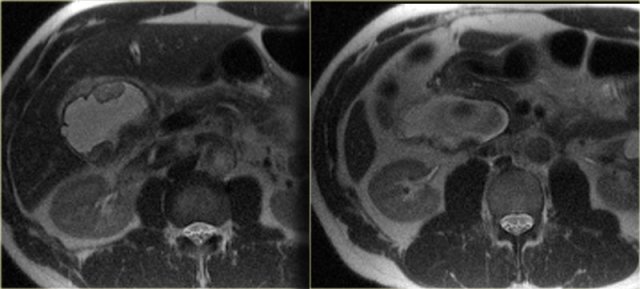

On the left a patient with dilated bile ducts with intraductal stones (arrow)

Study the image on the left.

Then continue reading.

The findings are:

- Medullary sponge kidney with stone formation (red arrow)

- Mild bile duct dilatation (blue arrow)

- Round hypoattenuating mass in the right liver lobe

The mass in the right lobe of the liver turned out to be an abscess.

Remember that liver abscesses in the early phase can look quite solid.

In the differential diagnosis we would also have to include a neoplasm, because patients with Caroli disease have an increased risk of developing a cholangiocarcinoma.